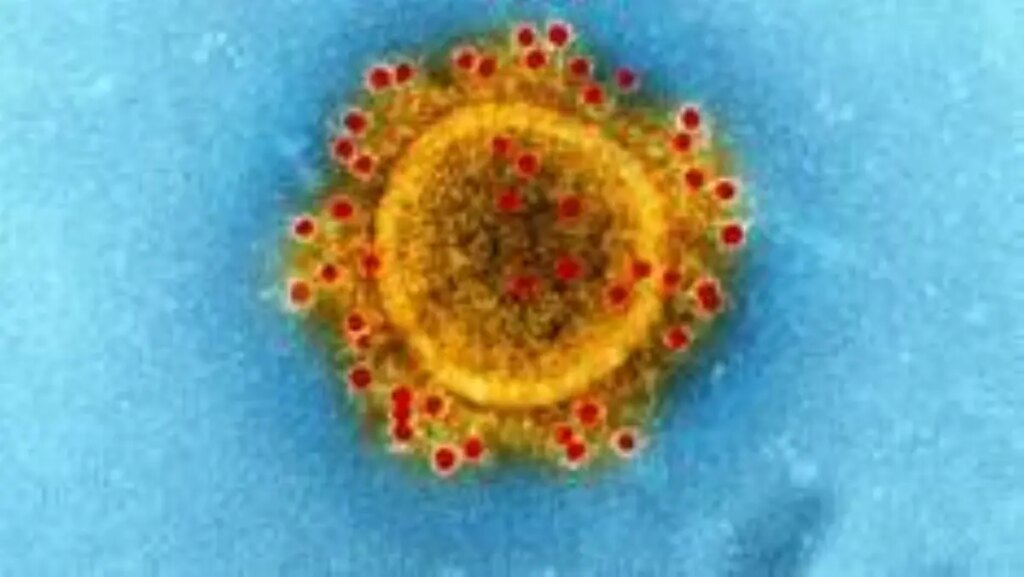

Bilim insanları, bu virüsü başkalarından ayırmak için “yeni koronavirüs” olarak isimlendirdi. Koronavirüslere, bu isim, mikroskoptan bakıldığnda, taç biçiminde görüldükleri için verildi.